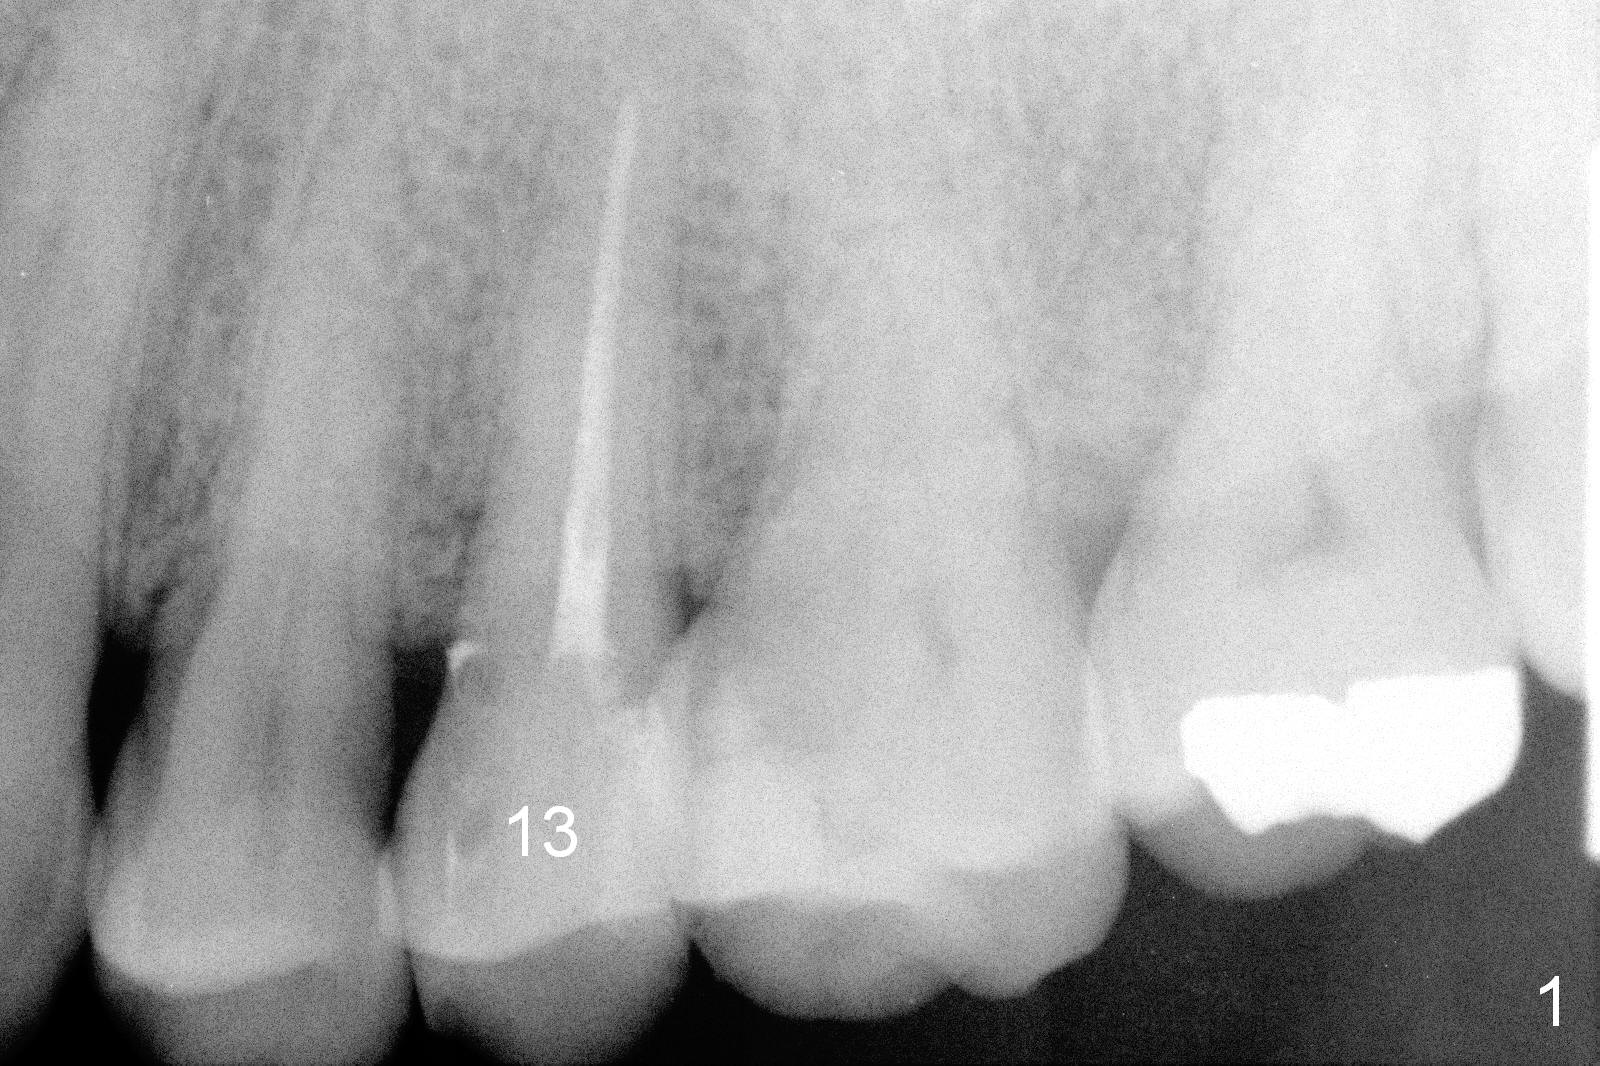

A 48-year-old man (CM) finished root canal therapy for the tooth #13 2.5 years ago (Fig.1). The tooth fractured lately (Fig.2). In spite of the fact that there is no periapical radiolucency in the most recent PA (Fig.3), the socket will be treated with No Antibiotic. Osteotomy is initiated at the junction of the lower and middle thirds of the palatal wall. The palatal cusp subgingival fracture may cause bone resorption in the palatal wall (at the crest). A 14 (Fig.4) or 13.5 (Fig.5) mm bone-level implant is probably going to have 8 mm contact with new bone.